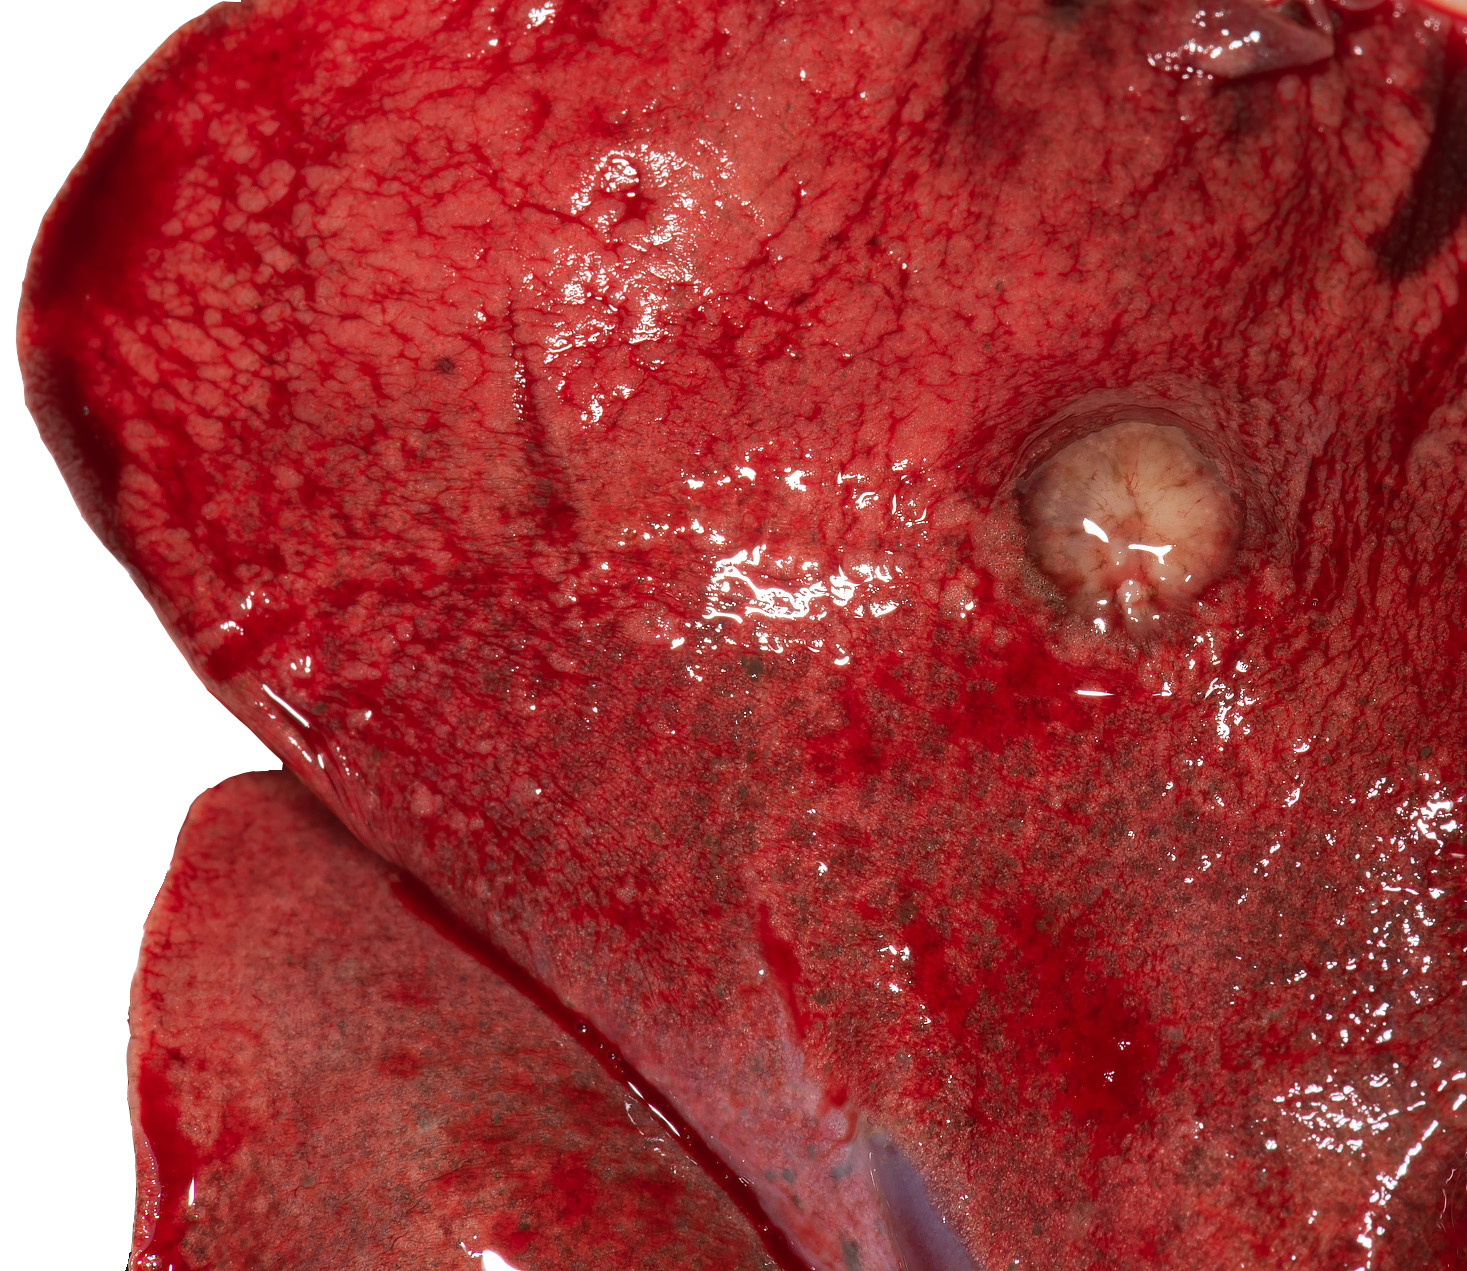

Bij de sectie waren meerdere knobbeltjes in de longen te zien. Dergelijke knobbeltjes kunnen door diverse ziekten worden veroorzaakt, waaronder runder-tuberculose. Dat is als eerste onderzocht en uitgesloten. Verder onderzoek van het longweefsel onder de microscoop toonde aan dat de knobbeltjes tumoren waren. Het microscopisch beeld van de tumor duidde erop dat het type longtumor, behoort tot de zogenaamde niet-kleincellige longkanker, een plaveiselcelcarcinoom. De lever vertoonde ontstekingshaarden passend bij rondtrekkende wormlarven.